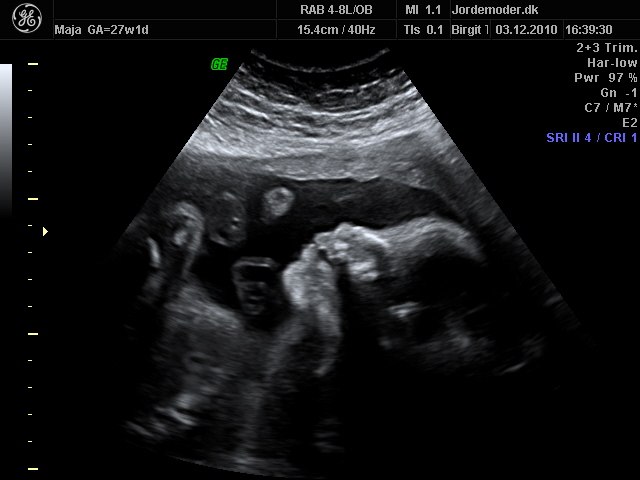

billede 7 - 27+1

billede 8 - 27+1 3d